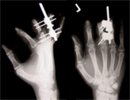

2nd surgery to lengthen index and ring fingers

Lengthening all 3 amputated fingers with satisfied patient